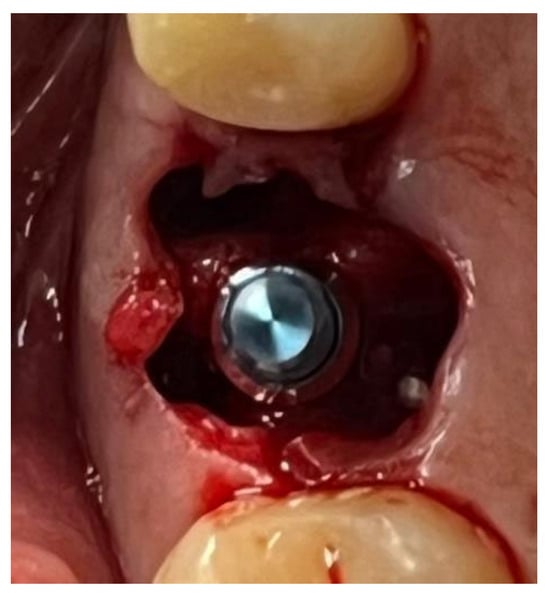

In a 49-year-old patient with ischemic heart disease, Glubran II was used as a stabilizing material for natural bone graft granules at a site rehabilitated with implant-prosthetic treatment, with the aim of achieving volumetric enhancement of the buccal bone. Following specific guidelines for surgical treatment of ischemic heart disease (4), implant therapy was carried out (Figure 8). Natural bone graft material (Bio-Oss®—Geistlich, Baden-Baden, Germany) was applied and stabilized with Glubran II. The application was made using an endodontic needle, depositing single droplets of the glue to cover the entire graft material before placing the prepared flap on top (Figure 9). This technique achieved stable graft fixation at the recipient site, demonstrating the efficacy of Glubran II for internal use (Figure 10).

Figure 8. Implant-prosthetic rehabilitation at site 36; buccal bone level prior to regenerative techniques.

Figure 9. Stabilization of bone regeneration material with Glubran II.

Figure 10. Surgical site at the end of the polymerization time of Glubran II; the site was subjected to tensile testing, with positive results under the applied tensions.